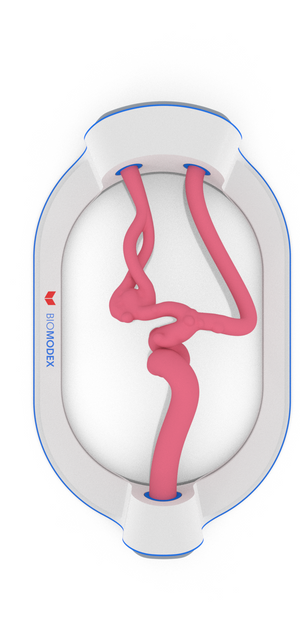

{"id":7922838864035,"title":"EVIAS-HMS-Cartridge- #181-AAH","handle":"evias-hms-cartridge-181-aah","description":"\u003cp\u003e\u003cbr\u003e\u003c\/p\u003e","published_at":"2022-12-05T20:09:59+01:00","created_at":"2022-12-05T20:10:05+01:00","vendor":"BIOMODEX®","type":"NEU Cartridge","tags":["Aneurysm Type_Bifurcation","Cartridge Type_Aneurysm","EVIAS","Generic","Location_MCA"],"price":75000,"price_min":75000,"price_max":75000,"available":true,"price_varies":false,"compare_at_price":null,"compare_at_price_min":0,"compare_at_price_max":0,"compare_at_price_varies":false,"variants":[{"id":43115836506275,"title":"Invivotech (pink)","option1":"Invivotech (pink)","option2":null,"option3":null,"sku":"NEUR-CA-SA-A-0181-AAHA","requires_shipping":true,"taxable":true,"featured_image":null,"available":true,"name":"EVIAS-HMS-Cartridge- #181-AAH - Invivotech (pink)","public_title":"Invivotech (pink)","options":["Invivotech (pink)"],"price":75000,"weight":116,"compare_at_price":null,"inventory_management":"shopify","barcode":"EVIAS-HMS-Training Cartridge-0181","requires_selling_plan":false,"selling_plan_allocations":[]},{"id":43115836539043,"title":"Clear","option1":"Clear","option2":null,"option3":null,"sku":"NEUR-CA-KT-A-0181-AAH-T","requires_shipping":true,"taxable":true,"featured_image":null,"available":true,"name":"EVIAS-HMS-Cartridge- #181-AAH - Clear","public_title":"Clear","options":["Clear"],"price":75000,"weight":116,"compare_at_price":null,"inventory_management":"shopify","barcode":"EVIAS-HMS-Training Cartridge-0181","requires_selling_plan":false,"selling_plan_allocations":[]}],"images":["\/\/orders-emea.biomodex.com\/cdn\/shop\/products\/A-0181_Top_84e47b01-8c4c-4008-a546-fdca5cc22659.png?v=1670267405","\/\/orders-emea.biomodex.com\/cdn\/shop\/products\/A-0181_Side_a7ef3639-3764-4428-9ae6-6d42207d75e0.png?v=1670267405","\/\/orders-emea.biomodex.com\/cdn\/shop\/products\/A-0181_Iso_2_68cf79aa-3396-458a-826f-f8a9d6ca03e0.png?v=1670267405","\/\/orders-emea.biomodex.com\/cdn\/shop\/products\/A-0181_Iso_1_8728d918-dd8d-442e-aea6-aeb9b07edfc1.png?v=1670267405"],"featured_image":"\/\/orders-emea.biomodex.com\/cdn\/shop\/products\/A-0181_Top_84e47b01-8c4c-4008-a546-fdca5cc22659.png?v=1670267405","options":["Material"],"media":[{"alt":null,"id":28675815768227,"position":1,"preview_image":{"aspect_ratio":0.468,"height":1916,"width":897,"src":"\/\/orders-emea.biomodex.com\/cdn\/shop\/products\/A-0181_Top_84e47b01-8c4c-4008-a546-fdca5cc22659.png?v=1670267405"},"aspect_ratio":0.468,"height":1916,"media_type":"image","src":"\/\/orders-emea.biomodex.com\/cdn\/shop\/products\/A-0181_Top_84e47b01-8c4c-4008-a546-fdca5cc22659.png?v=1670267405","width":897},{"alt":null,"id":28675815800995,"position":2,"preview_image":{"aspect_ratio":2.136,"height":897,"width":1916,"src":"\/\/orders-emea.biomodex.com\/cdn\/shop\/products\/A-0181_Side_a7ef3639-3764-4428-9ae6-6d42207d75e0.png?v=1670267405"},"aspect_ratio":2.136,"height":897,"media_type":"image","src":"\/\/orders-emea.biomodex.com\/cdn\/shop\/products\/A-0181_Side_a7ef3639-3764-4428-9ae6-6d42207d75e0.png?v=1670267405","width":1916},{"alt":null,"id":28675815833763,"position":3,"preview_image":{"aspect_ratio":2.136,"height":897,"width":1916,"src":"\/\/orders-emea.biomodex.com\/cdn\/shop\/products\/A-0181_Iso_2_68cf79aa-3396-458a-826f-f8a9d6ca03e0.png?v=1670267405"},"aspect_ratio":2.136,"height":897,"media_type":"image","src":"\/\/orders-emea.biomodex.com\/cdn\/shop\/products\/A-0181_Iso_2_68cf79aa-3396-458a-826f-f8a9d6ca03e0.png?v=1670267405","width":1916},{"alt":null,"id":28675815866531,"position":4,"preview_image":{"aspect_ratio":2.136,"height":897,"width":1916,"src":"\/\/orders-emea.biomodex.com\/cdn\/shop\/products\/A-0181_Iso_1_8728d918-dd8d-442e-aea6-aeb9b07edfc1.png?v=1670267405"},"aspect_ratio":2.136,"height":897,"media_type":"image","src":"\/\/orders-emea.biomodex.com\/cdn\/shop\/products\/A-0181_Iso_1_8728d918-dd8d-442e-aea6-aeb9b07edfc1.png?v=1670267405","width":1916}],"requires_selling_plan":false,"selling_plan_groups":[],"content":"\u003cp\u003e\u003cbr\u003e\u003c\/p\u003e"}